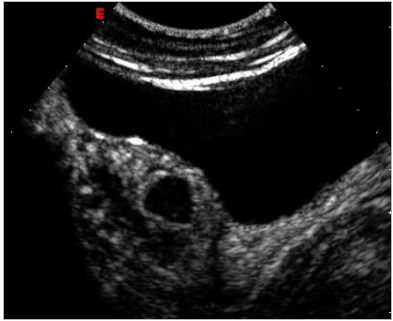

治療后壞死的子宮肌瘤不會(huì)消失,而是會(huì)發(fā)生纖維化,緩慢縮小,但對(duì)人體已經(jīng)沒(méi)有危害了。最近,由于磁共振增強(qiáng)掃描(圖1,2)和超聲造影檢查技術(shù)(圖3,4)的應(yīng)用,使治療效果的評(píng)價(jià)更加客觀和明確。

圖4 治療后6個(gè)月超聲造影